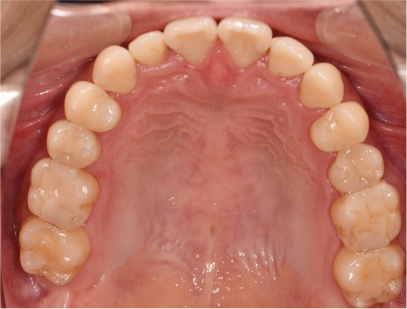

症例02|20代の男子

前歯部の反対咬合の症例

上下の前歯が反対咬合を主訴として来院されました。通常通り検査を行い「反対咬合」と診断されました。

治療計画

下の犬歯から後ろの歯をまずは後方に移動して、その後に上下の歯並びを綺麗に並べて前歯部の咬み合わせを改善することにしました。

矯正の種類

カリエールディスタライザー、上に裏側、下に表側のセラミック(白い矯正装置)

治療前の写真を治療後の写真を比べると、鼻の下がくぼんでいたのが改善されて口元が綺麗になった事が解ります。また歯並びは綺麗に並び上の歯が前に出て下の歯が後ろに移動して歯がしっかりと咬み合っています。

患者様に協力いただけたため、2年の治療期間で終了することができました。